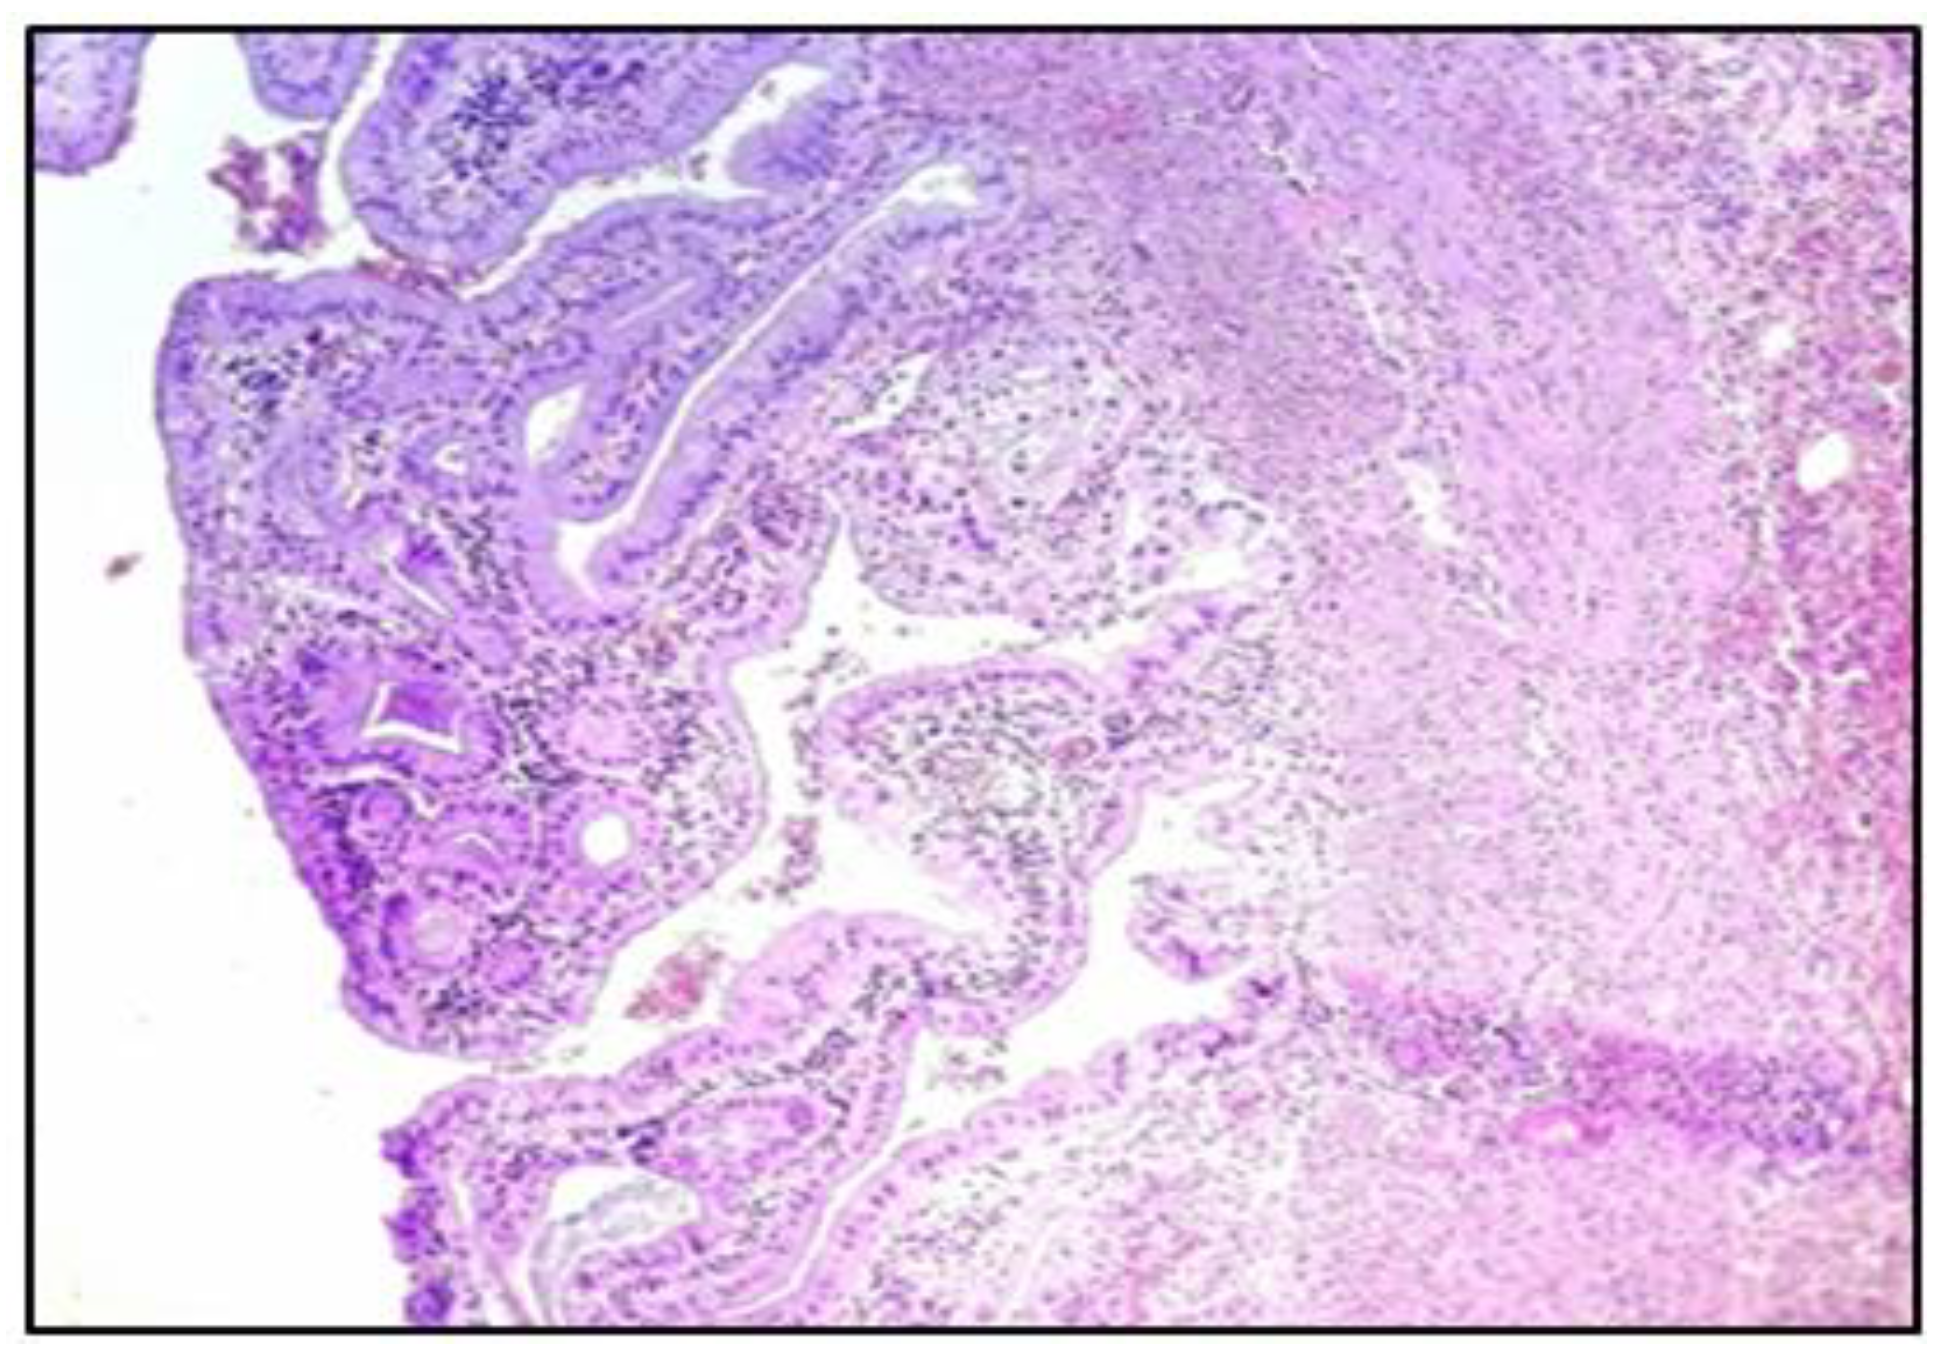

- The confirmation by histopathological examination of the existence of micro-thrombi in the gallbladder vasculature, with necrosis and its perforation, supports the recent studies that mention the occurrence of coagulation disorders in Covid-19-positive patients.